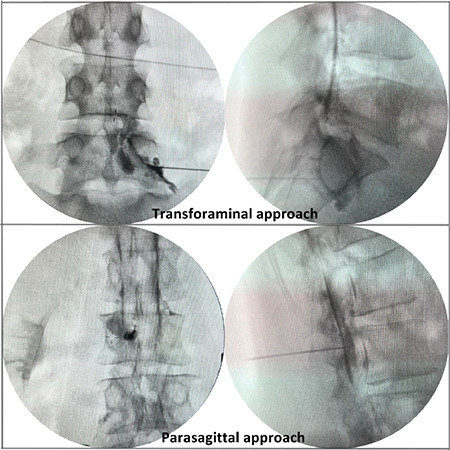

Objective: This study aimed to compare parasagittal interlaminar (PS) and transforaminal (TF) epidural steroid injections for unilateral L5 and S1 radicular lower back pain in terms of patient comfort, efficacy, safety, contrast enhancement, and radiation exposure.

Methods: This was a prospective randomized single-blind study. A total of 59 participants were included in this study. The visual analog scale (VAS) and Oswestry Disability Index (ODI) were obtained. A comfort questionnaire was administered to all participants. The total fluoroscopy time and contrast distribution levels were recorded.

Results: Pre- and post-treatment VAS scores were similar between the groups. The ODI scores increased in favor of the PS group at week 2 (P < 0.041); however, there was no difference between the two groups at other times. The VAS and ODI scores improved significantly with treatment in both the groups (P < 0.001). Total fluoroscopy time was shorter in the PS group (P < 0.001). PS application was more comfortable (P < 0.001). While no complications were observed in the PS group, three complications occurred in the TF group. Anterior epidural contrast spread to three or more levels was observed in 57% of the participants in the PS group, whereas no spread to more than two levels was observed in the TF group.

Conclusion: The PS epidural approach is superior to the TF approach in terms of a low incidence of side effects, less radiation exposure, better patient comfort, higher epidural contrast spread, and single-level needle access.